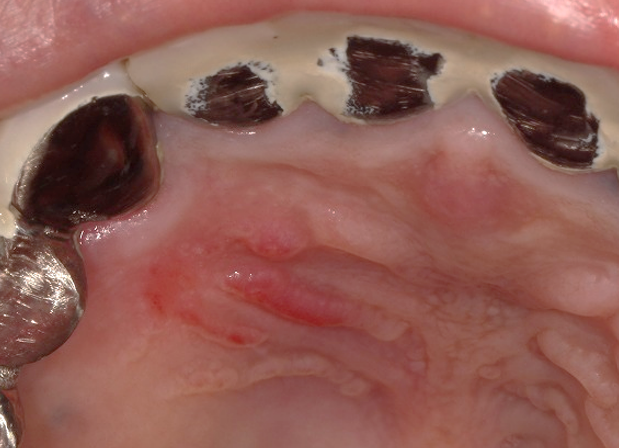

口内炎画像 (312 無料画像)

口内炎画像